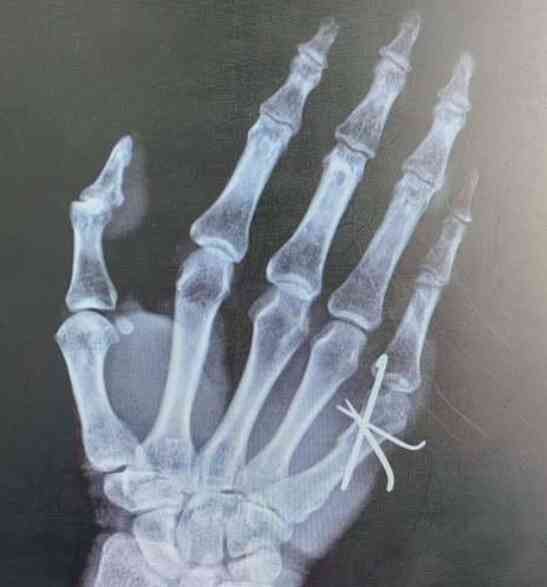

掌骨骨折是手部骨折中一种较为常见的类型,通常发生在不慎跌倒时手部用力支撑地面,或是拳击等高冲击力活动中。在一份手术记录和麻醉报告中,患者因右手第五掌骨骨折接受了闭合复位克氏针内固定术。手术采用神经

此次医学报告中的主要诊断为右手第三掌骨骨折。除此之外,还伴随有烫伤后遗症手掌挛缩畸形、骨质疏松症、以及其他疾病如双肺炎性结节、胃底区结节和周围神经损伤。掌骨骨折是手部常见的骨折类型之一,尤其在外伤后发

根据此次的检查报告及结果显示,患者被诊断为左手第5掌骨近端骨折,且骨折断端错位、重叠明显,伴随邻近软组织广泛肿胀。报告中显示的异常指标包括骨折部位的移位和软组织肿胀,这些与正常状态明显不同。正常情况下